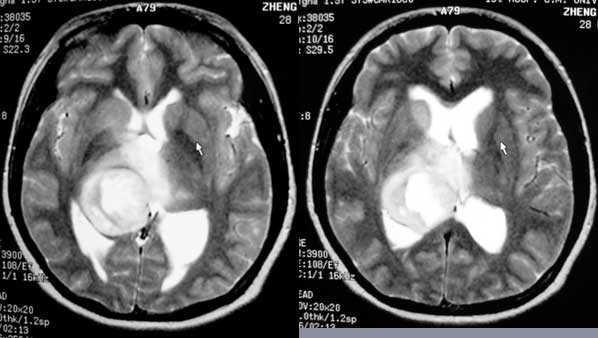

女性,28岁。头痛请会诊

右侧丘脑类圆形等t1,长t2病灶,t1增强明显强化。

女性,28岁。头痛请会诊。

考虑:①丘脑胶质瘤可能大。②脑积水。

t1等信号内出现点状高信号,考虑为出血灶,肿块内侧可见弧形低信号,为脑积液影。长t2,其内有混杂信号,周壁强化明显,内不规则强化,生长位置似在右侧丘脑,又似在来源于侧脑室,故脉络丛乳头状瘤不排外。

右侧丘脑胶质瘤?右侧脑室内的异常信号如何解释?不会是丘脑出血破入脑室?